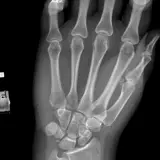

MSK Radiographs

Peds Radiographs